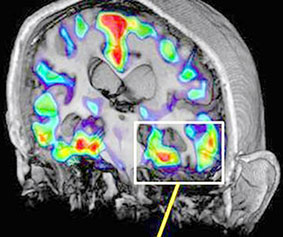

Kỹ thuật quét não mới phát hiện sớm tác nhân gây bệnh Alzheimer